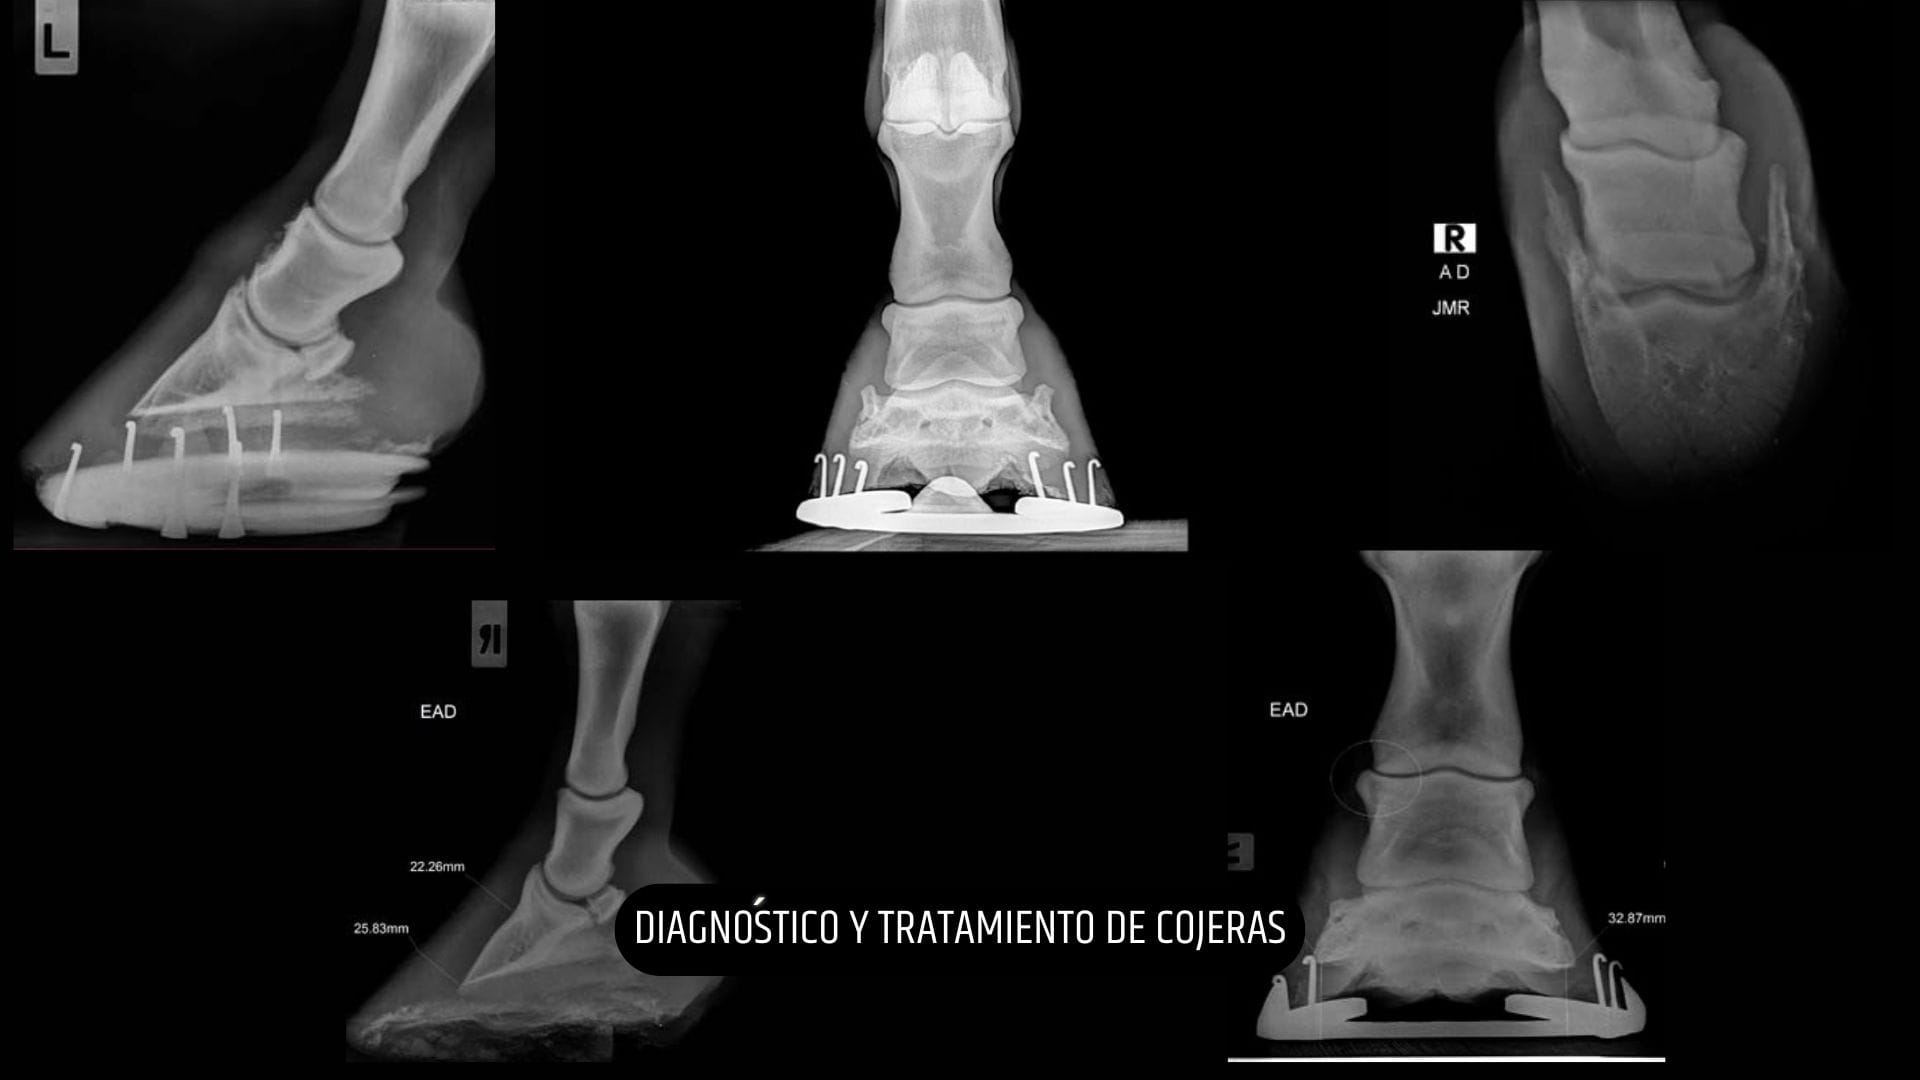

Experto en exámenes pre-compra, diagnóstico por imagen y odontología equina

Contamos con el último equipamiento para la realización de pruebas médicas, radiografías, ecografías, tratamientos de plasma...

A continuación estuve durante un año adquiriendo formación en medicina deportiva y diagnóstico de cojeras con D. Juan Roldán Romero (Equinuvi) en Córdoba. Posteriormente realicé un internado de un año de duración en el Servicio de Clínica Equina del Centro Policlínico Veterinario Raspeig (Alicante) junto a D. Salvador Termes y D. Manuel A. Rodriguez.